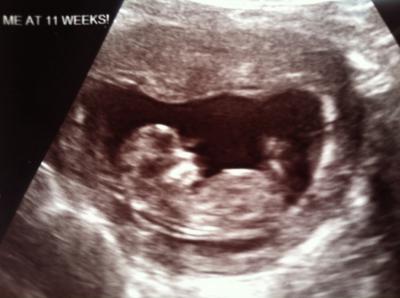

Huhu! Gestern war endlich unser lang ersehnter 2. FA Termin. Da ich nun hier in den USA schwanger geworden bin, ist es sowieso immer aufregend für mich, Arztgespräche auf englisch zu führen. Auch der Ablauf bei den Terminen bzw. Untersuchungen sind anders, als ich es aus Deutschland gewohnt bin (was nicht heißt, dass es schlechter ist). Da es unser erstes Kind ist, ist natürlich alles neu und spannend für uns. Gestern wurde erstmal ein rundum-check gemacht: Abstrich, Brust abtasten, Blutdruck messen und dann wurden meine Blutwerte besprochen (hatte letzte Woche Blut und Urin abgegeben). Alles soweit in Ordnung, eine leichte Blasenentzündung wurde festgestellt, mir wurde ein Antibiotikum verschrieben. Als mein FA mir sagte, dass für heute kein US vorgesehen sei (weil die Krankenkassen hier wohl nur 3 in der kompletten SS übernehmen), waren wir mehr als enttäuscht. Er wollte aber die Herztöne per Dopplergerät überprüfen. Er hat bestimmt 5 Minuten auf meinem Bauch hin und her gewischt...Nichts. Kein Herzton, kein leichtes, fernes Geräusch, Null. Mir schossen 1000 Gedanken durch den Kopf. Immer wieder haben mein Mann und ich uns verzweifelt angeschaut. Der FA versicherte zwar immer wieder, dass dies öfter vorkäme bei Frauen die noch nicht in der 14. Woche seien, aber an seinem Gesicht konnte ich sehen, dass er auch etwas beunruhigt war. Was für ein Horror!!! Er meinte dann, dass er aufgrund der Umstände nun doch einen Ultraschall anweist...das macht hier in seiner Praxis nicht er selbst sondern eine Spezialistin. Sie meinte gleich "kommt schnell mit, ich schieb euch dazwischen, kann aber nicht lange, sonst verschieben sich alle weiteren Termine." Mir war alles egal. Ich wollte nur mein Maikäferchen sehen und das Herz schlagen hören, und wenn nur für ein paar Sekunden. Ich lag also angespannt auf der Liege, der Ultraschall ging an, und da lag es...mein süßes Baby, so viel gewachsen seit dem letzten Termin vor 3 Wochen! Mein Atem hat gestockt bis sie endlich das Dopplergerät anschaltete und ich das Herzchen wie ein kleines Rennpferd galoppieren hörte....da sind mir erstmal die Tränchen die Wangen runter gelaufen!!! Was für ein Schreck... Alles soweit in Ordnung. Anbei das Foto...am Freitag haben wir im Krankenhaus die Nackenfaltenmessung. Das wird sicher nochmal nervenaufreibend!!

Bild zu Kleiner Schockmoment beim FA - Forum für Mai - Mamis